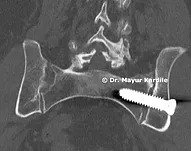

Anterior Cervical Discectomy & Fusion

ACDF

Anterior Cervical Discectomy and Fusion to treat cervical radiculopathy, disc herniation, and nerve compression in the neck.